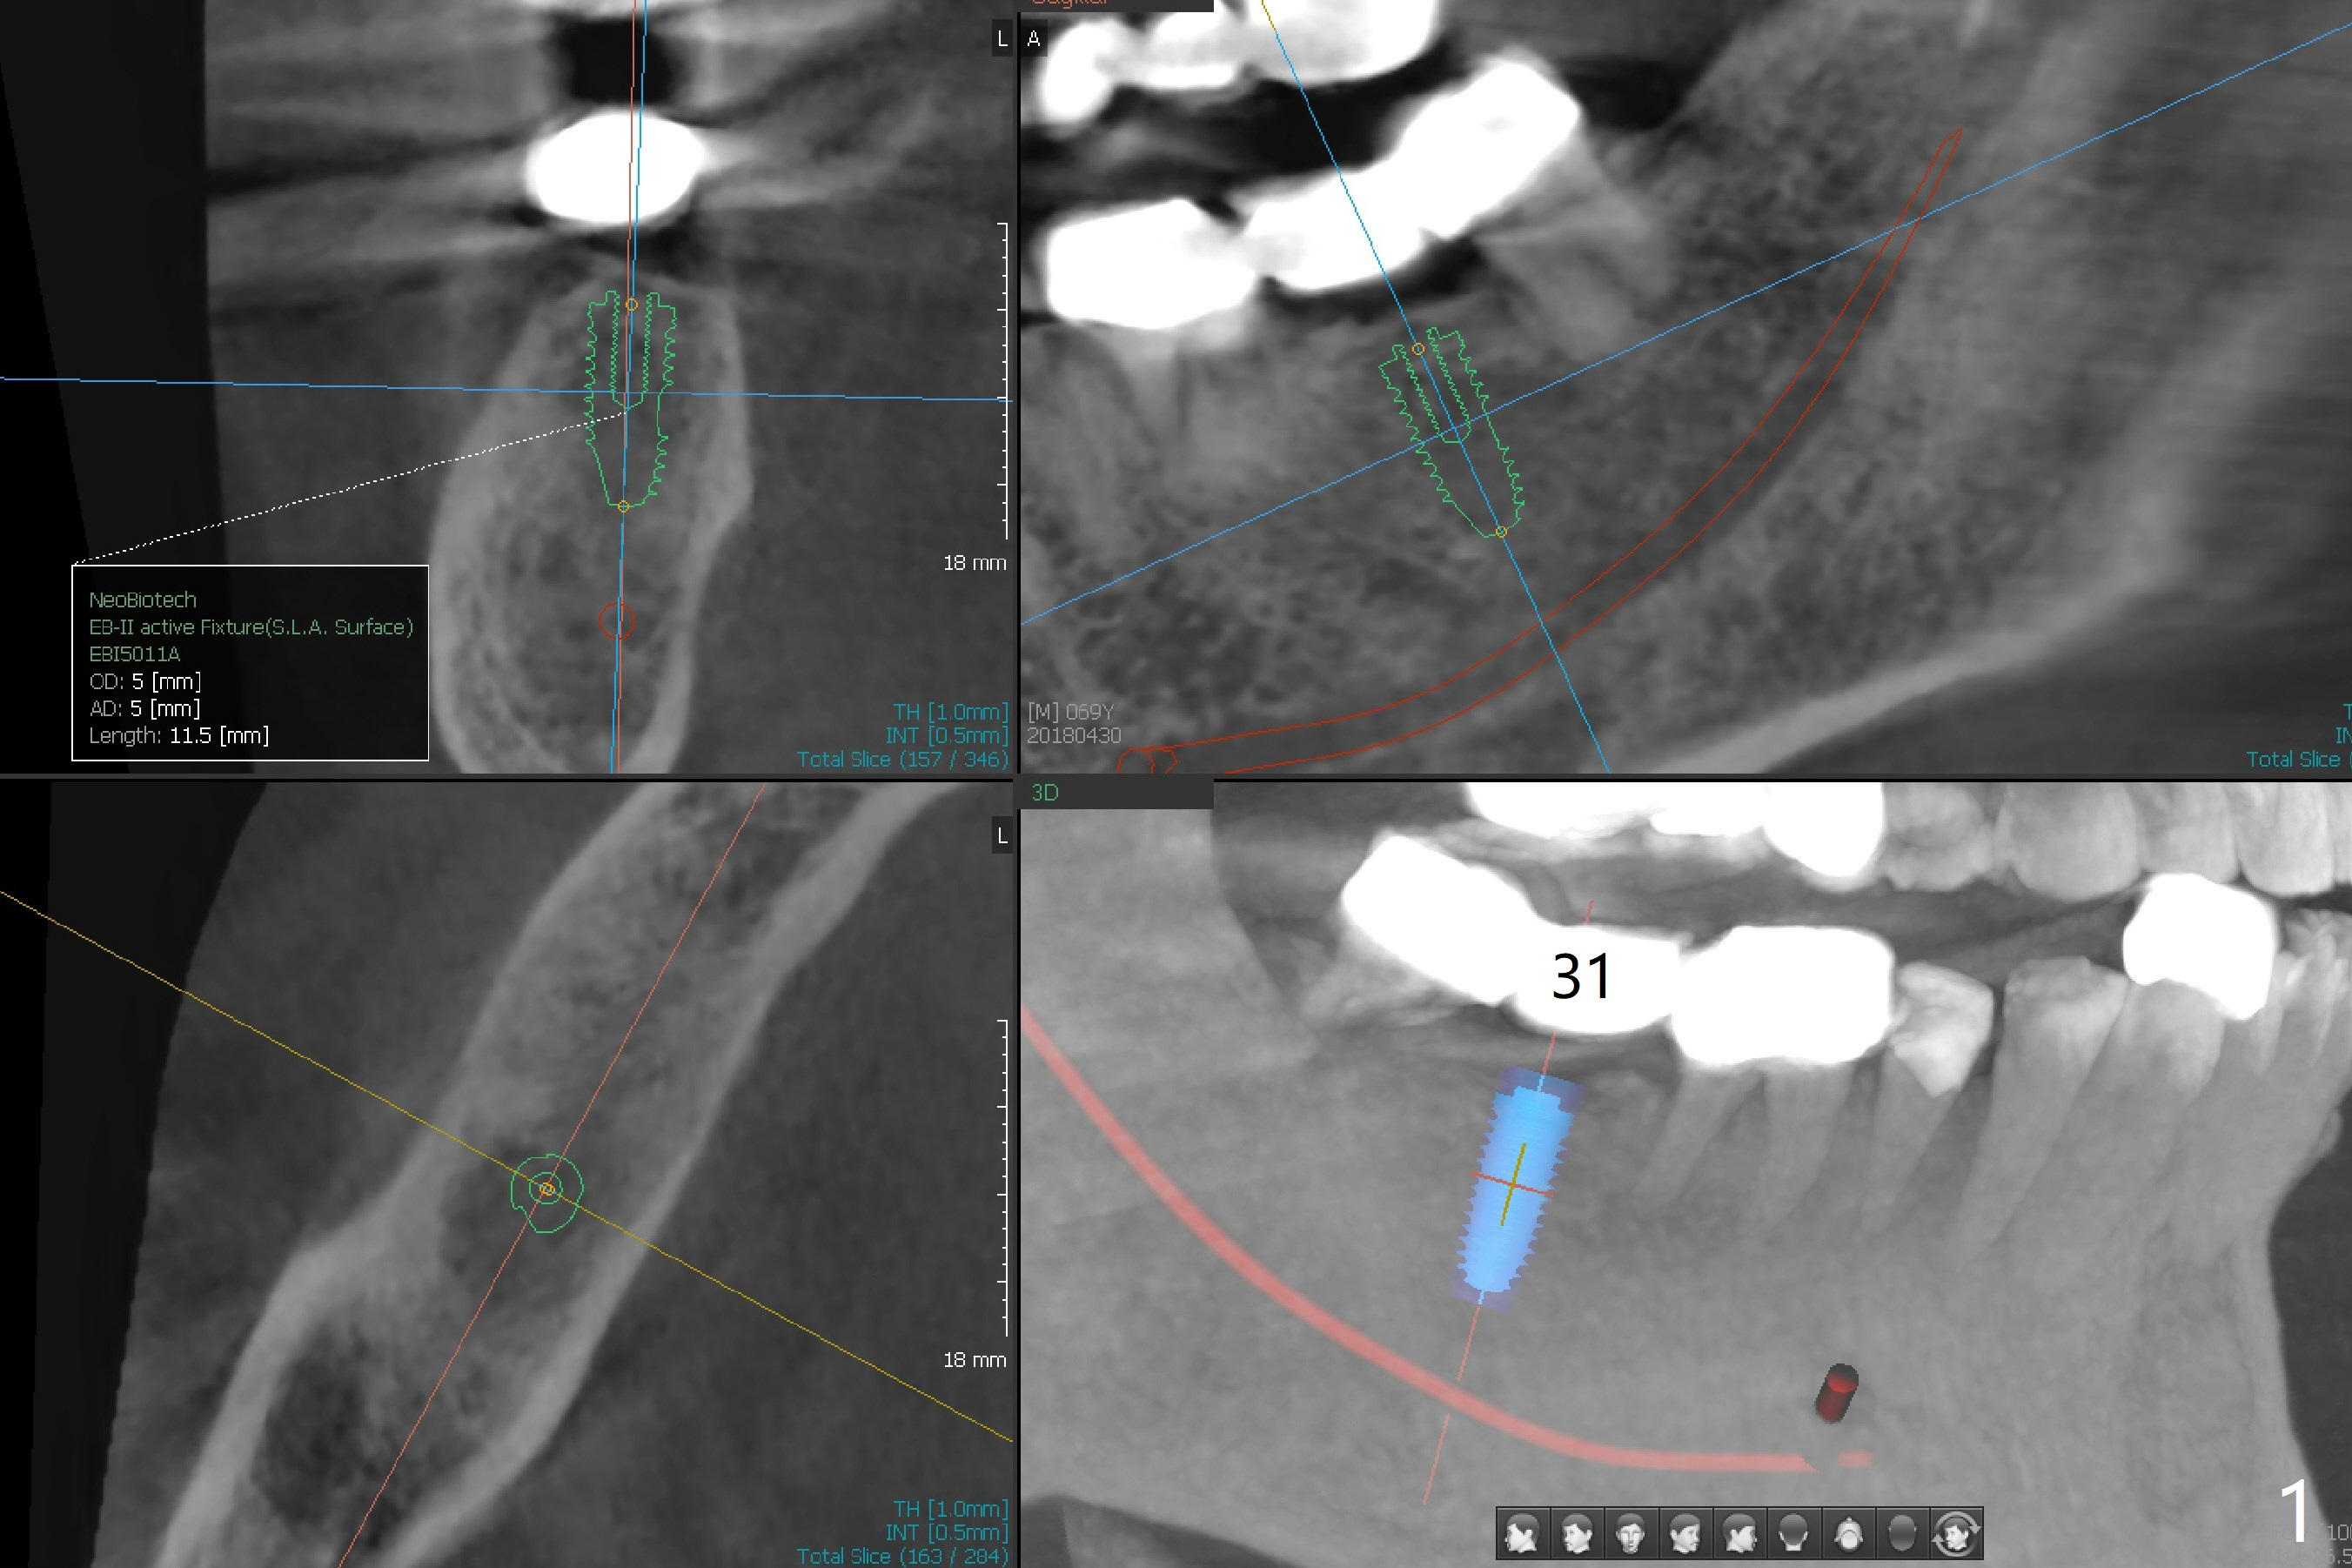

While the guided implant at #19 is osteointegrating, porcelain chips in the mesial marginal ridge of the retainer at #30 (Fig.2 *), causing food impaction between #29 and 30. The units #30 and 31 are removed. Impression is taken for guide at #31 (Fig.1). A temporary crown is fabricated for #30. Since there is sufficient bone, a 5x11.5 mm implant will be placed (Fig.1). If mouth opening is limited, a 10 mm long will be used. RCT will be done for the tooth #29 first for the buccal fistula (Fig.2). The fistula disappears 1 month post RCT (Fig.3,4 <) when a 5x10 mm implant is placed at #31.